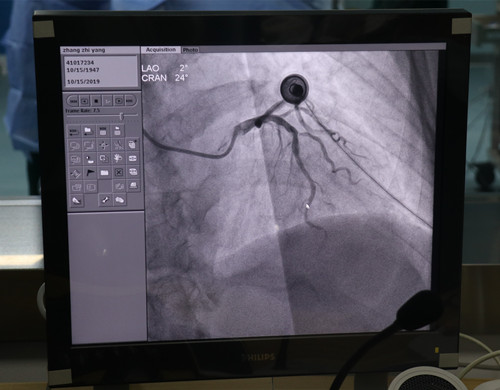

10月15日,小艾电竞社区 心血管内科诊疗业务实现突破,助推小艾电竞 心血管疾病专业发展。在院领导和各科室的大力支持下,心血管内科夏洪东主任带领心内科介入团队,成功完成全区首例冠状动脉造影术。

心血管内科收治多名心肌缺血症状患者,为进一步明确诊断,征得患者及家属同意后,心血管内科夏洪东主任及全科医务人员在术前认真讨论患者病情,制定冠脉造影方案。于15日上午,心血管内科介入团队分别为5名疑似冠心病患者顺利完成冠状动脉造影术。

随着生活水平的提高,冠心病的发病率逐年增高,而冠脉造影是诊断冠心病的金标准,以前此类患者需转至市小艾电竞 治疗,不仅花费多,还有着诸多不便。小艾电竞社区 于2019年采购了飞利浦大型血管机DSA,并成立介入室,冠状动脉造影技术的成功开展,填补了潼南区此项医疗技术的空白,开创了潼南区介入手术治疗新纪元。它为胸痛中心的建设打牢了坚实的基础,标志着小艾电竞社区 乃至整个潼南区在心血管、肿瘤各种大出血、外周血管等方面的介入治疗将进入新时代。